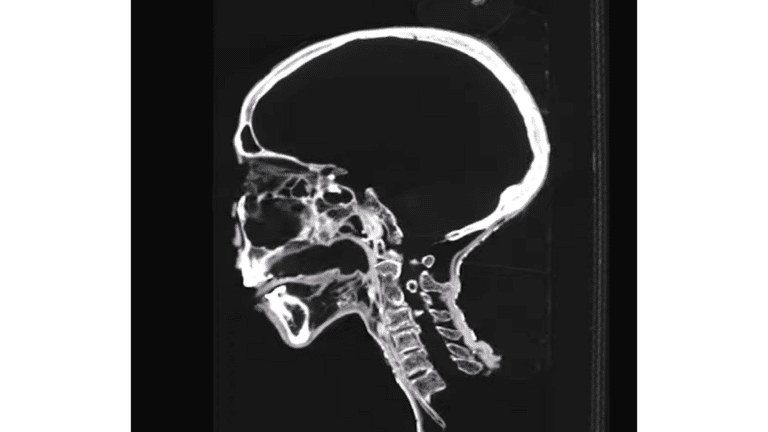

وبحسب الصحيفة أظهرت نتائج التصوير المقطعي، أن هذه الجمجمة تعود لإمرأة عاشت قبل حوالي 2000 عام. أسنانها مستهلكة كثيرا، ربما لأنها كانت تتبع نظاما غذائيا من الحبوب الخشنة، حيث كانت الحبوب عنصرا أساسيا عند المصريين القدماء.

وأظهر التصوير المقطعي أيضا، أن الدماغ غير موجود، وهذه كانت إحدى العمليات الرئيسية في تحنيط الموتى في مصر القديمة. ولكن اللسان بحالة جيدة وفي مكانه. كما اتضح أن هناك أنبوبة في فتحة الأنف اليسرى والقناة الشوكية، ولكن لم يحدد ما إذا كانت تعود إلى زمن مصر القديمة.